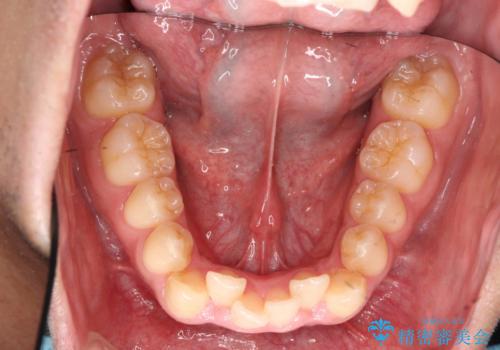

歯を抜かない矯正 奥歯のすれ違い咬合 下の八重歯

- 前歯のガタガタを主訴に来院。

奥歯はすれ違ってしまっていました。

口元も出ておらず、非抜歯を希望されたため、IPR(歯を削る処置)でスペースを確保しました。

上顎両側7番(一番奥の歯)はすれ違っており、虫歯になっていました。